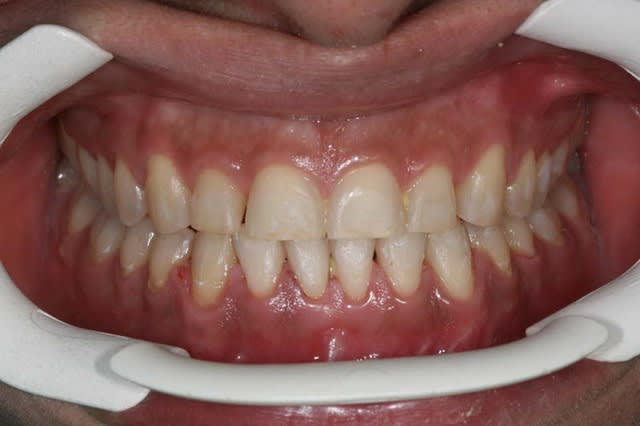

je la traite par les techniques de friction faible, et voici le résultat 1 an après

je ne suis pas en inversé d’articulé Ant. comme je pensais me retrouver !!!

et son profil s’est bien modifié

On voit bien le changement de profil sur les radios .

tu as réussi à lui avancer le point A?

ou alors c'est du à une légère version incisive supérieure + un soutien de la lèvre supérieure amélioré par l'épaisseur des brackets

"""ou alors c'est du à une légère version incisive supérieure + un soutien de la lèvre supérieure amélioré par l'épaisseur des brackets"""

arc et Bk. ne modifient pas un angle naso-nasal, les tissus mous ont un énorme potentiel d’adaptation (fait des photos de profil de tes patients 3 mois après la pose de ton matériel et tu verras toi-m que le matériel ne change pas un profil, encore une fausse idée reçue)

pas plus qu’ils ne modifient les lèvres, regarde bien l’évolution du volume des lèvres de ma patiente, ce n’est pas un matériel qui peut faire ça

peut être, avec une légère version des Inc. Sup., mais ce n’est pas ce que je voulais faire.

Ce cas a été traité en Burstone (technique délicate) par un praticien dont la réputation n’est plus à faire, et qui de surcroit enseigne cette technique. Je n’imaginais pas faire mieux, cela s’est fait sans moi

De plus en plus, je crois que j’ai été trop directif dans mes TTT., il se passe, avec les frictions faibles et les forces faibles, des phénomènes biologiques encore inexpliqués, mais ce n’est pas pour cela qu’il faut les rejeter